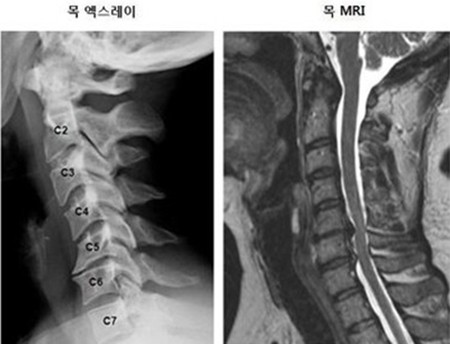

목디스크 증상이 심해지기 전에 정기적인 건강 검진을 통해 상태를 점검하는 것이 좋습니다. 특히 목과 관련된 문제가 있을 경우 전문의와 상담하여 필요할 경우 물리치료나 약물 치료를 받는 것이 중요합니다.

전문가의 도움을 통해 적절한 치료 방법을 찾고, 유지 관리하는 것은 목디스크뿐만 아니라 전반적인 건강을 지키는 데 큰 도움이 될 것입니다. 자가 진단이나 자가 치료보다 전문의와 상담하는 것이 가장 바람직합니다.